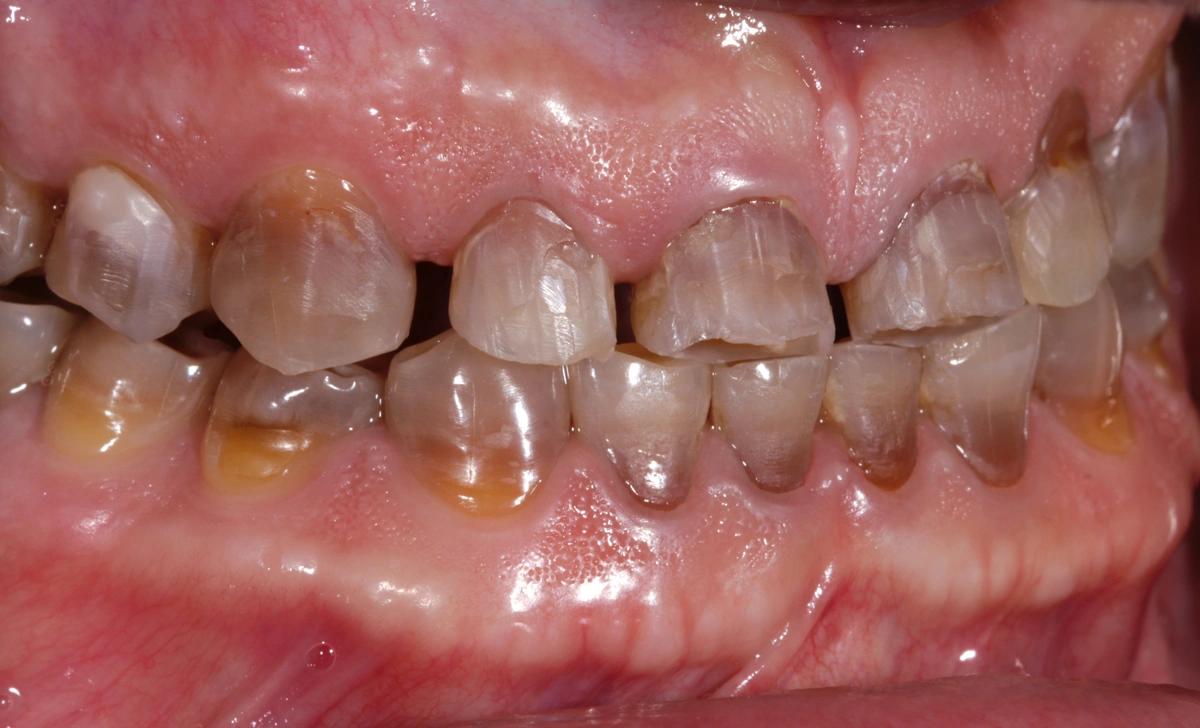

Paciente joven acude a consulta referido por el ortodoncista para tratamiento de desgaste.

La tetraciclina era un medicamento que se administraba en los años 50 que a posteriori se han podido observar los efectos secundarios que tienen en la boca: tinción dental intrínseca. Existen distintos grados y en función de su severidad. Las tinciones por tetraciclinas suponen un reto a nivel restaurador.

En este caso se trata de un paciente con desgaste dental severo y tinción por tetraciclinas grado IV.